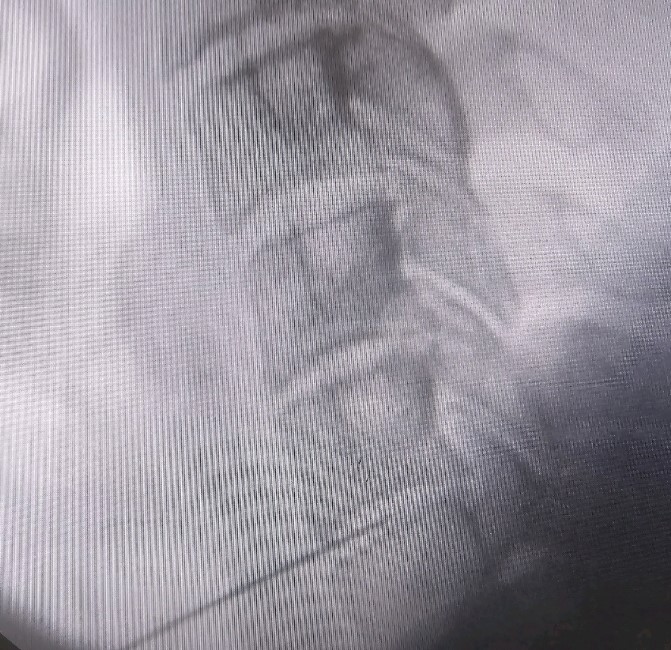

Η επέμβαση γίνεται κάτω από συνεχή ακτινοσκοπική καθοδήγηση με τον ασθενή σε πρηνή θέση και ήπια καταστολή. Εισάγεται μια ειδική βελόνη στον δίσκο και μέσω αυτής εισέρχεται ένας ειδικός καθετήρας που συνδέεται με τη γεννήτρια του μηχανήματος που χορηγεί την ενέργεια. η επερχόμενη μείωση της ενδοδισκικής πίεσης, προκαλεί την υποχώρηση της κήλης προς το κέντρο του δίσκου, μειώνοντας έτσι την πίεση της σύστοιχης νευρικής ρίζας. Σε μια επέμβαση δύναται να αντιμετωπισθούν έως και 3 επίπεδα δίσκου.

Η τεχνική εφαρμόζεται στην αυχενική μοίρα της σπονδυλικής στήλης με πρόσθια προσπέλαση και στην οσφυϊκή μοίρα με οπίσθια προσπέλαση, κάτω από ακτινοσκοπική καθοδήγηση και με χρήση σκιαγραφικής ουσίας για την απεικόνιση του δίσκου πριν την έναρξη της εξάχνωσης.